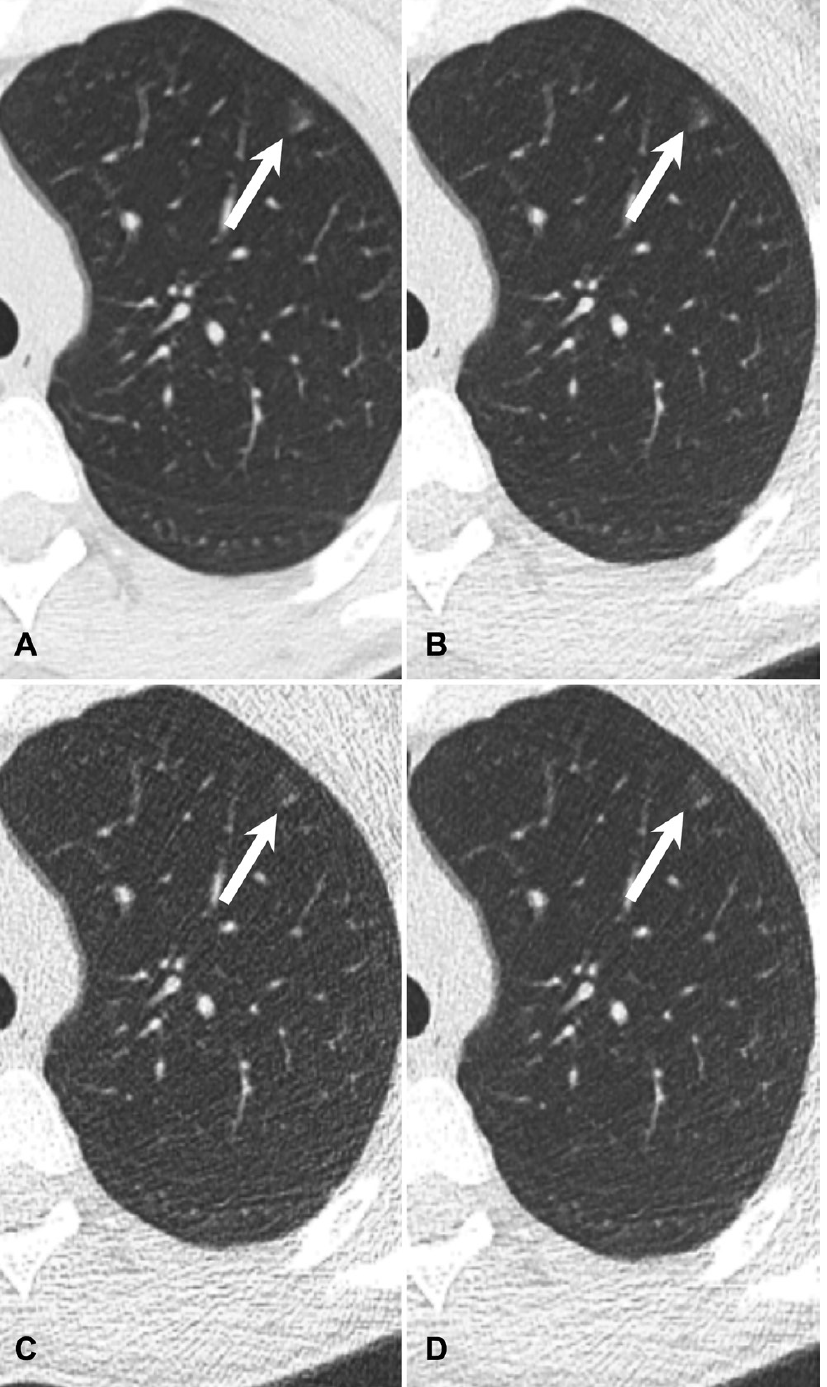

Chest MRI picks up the same characteristics of COVID-19 pneumonia that are seen on chest CT, making it a good alternative without the radiation.